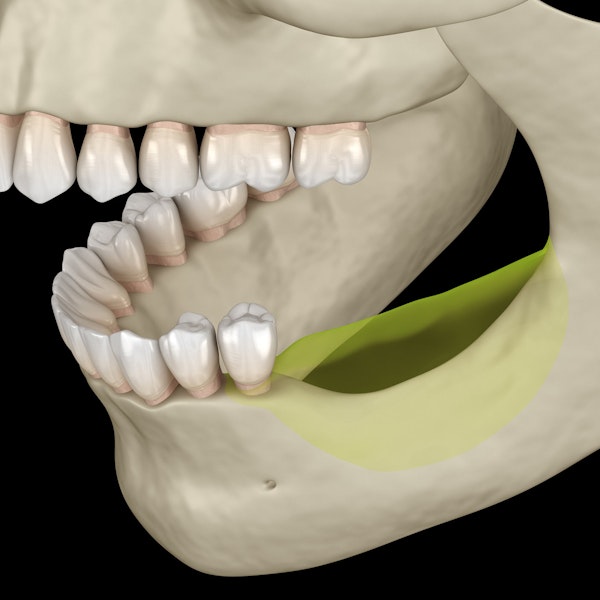

Bone loss in the jaw can have negative health effects and can prohibit patients from receiving necessary procedures like dental implants .

During bone grafting surgery, Dr. Polidori places grafting material in areas of the jaw where bone loss has occurred. He can transfer tissue from a part of your body that has more than enough bone, or use outside tissue replacements like a synthetic substitute.

The tissue placed during a graft creates necessary support for your bones and stimulates your body to create new, healthy jaw tissue. The formation of natural bone in areas where bone loss had occurred helps prevent oral deterioration and allows our Lakewood patients to receive the restorative dentistry procedures they desire.

Risks of Untreated Jawbone Loss